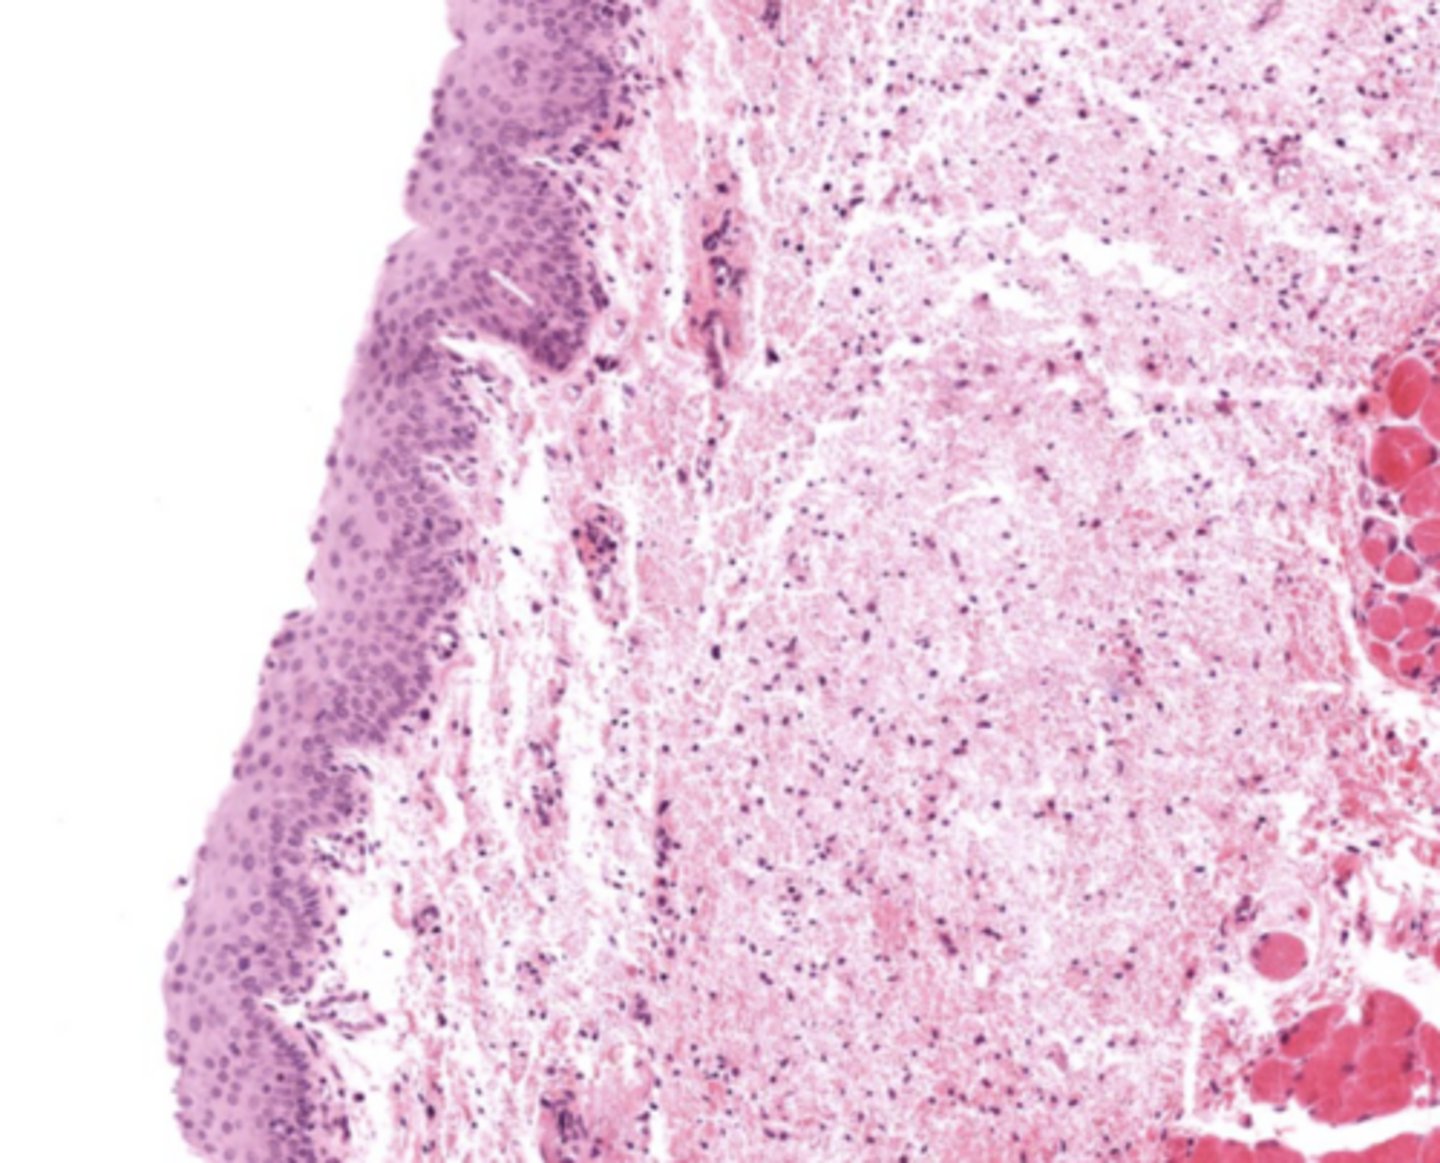

What epithelial transition occurs in the larynx?

Pseudostratified ciliated epithelium -> stratified squamous epithelium (image is at the vestibular folds)

Understand how the epithelium changes from epiglottis to treachea`

Epiglottis - stratified squamous epithelium with elastic cartilage

False vocal cords - pseudostra. cillated epithelium

True vocal cords - stratified sq. non keratinized epithelium with skeletal muscle

Describe the transitional epithelium of the larynx

The main transition occurs near the vocal cords, separating the squamous epithelium of the true vocal cords from the respiratory epithelium pseudostratified ciliated